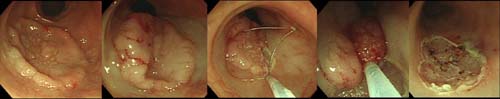

Áø´Ü°ú ³»½Ã°æÀû Á¡¸· ÀýÁ¦¼úÀ» ½ÃÇàÇϰí

ÀÖ½À´Ï´Ù. ´ÙÀ½Àº Á¶±â ´ëÀå¾Ï¿¡¼ ³»½Ã°æÀû

Á¡¸·ÀýÁ¦¼úÀ» ½ÃÇàÇÏ´Â Àå¸éÀÔ´Ï´Ù.